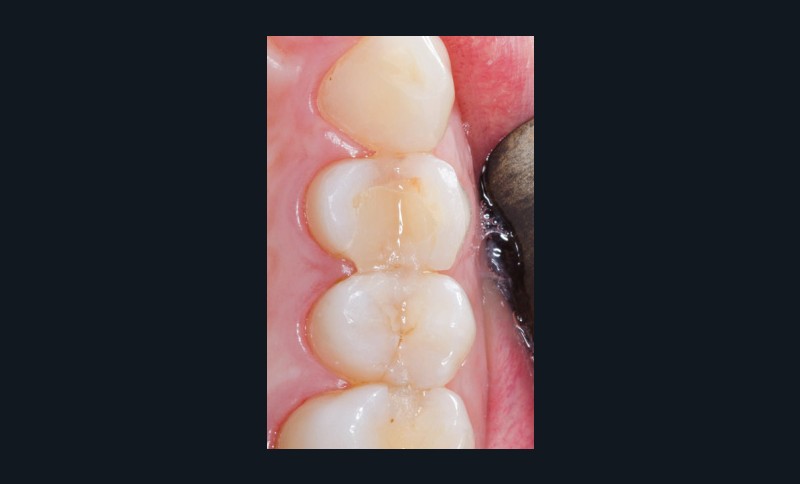

Enfin, un des derniers atouts de l’empreinte optique est la possibilité de réaliser des empreintes des préparations sous digue, ce qui diminue encore les risques d’infiltration des préparations (fig. 5).